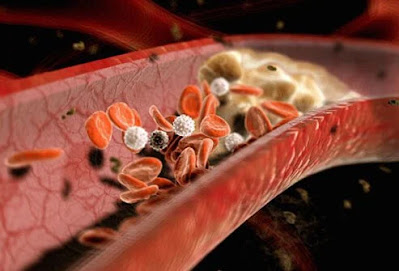

Η στεφανιαία νόσος εμφανίζεται όταν η πλάκα, μια κολλώδης ουσία, στενεύει ή εμποδίζει εν μέρει τις στεφανιαίες αρτηρίες (όπως το κολλώδες υλικό που βουλώνει ένα καλαμάκι) και μπορεί να οδηγήσει σε μειωμένη ροή αίματος. Αυτή η μειωμένη ροή αίματος μπορεί να προκαλέσει πόνο στο στήθος (στηθάγχη), ένα προειδοποιητικό σημάδι πιθανών καρδιακών προβλημάτων όπως καρδιακή προσβολή. Η πλάκα μπορεί επίσης να παγιδεύσει μικρούς θρόμβους αίματος, εμποδίζοντας εντελώς μια στεφανιαία αρτηρία ξαφνικά, με αποτέλεσμα καρδιακή προσβολή.

Πώς η πλάκα, οι θρόμβοι αίματος μπορούν να προκαλέσουν καρδιακή προσβολή

Οι ρήξεις πλακών μπορεί να προκαλέσουν το σχηματισμό θρόμβων που εμποδίζουν την αρτηριακή ροή αίματος.

Η πλάκα μπορεί να εμφανιστεί στις στεφανιαίες και άλλες αρτηρίες (για παράδειγμα, στις καρωτιδικές αρτηρίες). Κάποια πλάκα μπορεί να είναι σκληρή ή σταθερή εξωτερικά, αλλά μαλακή και αφρώδης ή κολλώδης στο εσωτερικό. Εάν ανοίξει η σκληρή περιοχή που μοιάζει με κέλυφος, συστατικά αίματος όπως τα αιμοπετάλια και οι μικροί θρόμβοι σχηματίζουν έναν μεγάλο θρόμβο και εμποδίζουν αποτελεσματικά τη ροή του αίματος μέσω της αρτηρίας. Ο καρδιακός ιστός βρίσκεται χαμηλότερα από τον θρόμβο στη συνέχεια, υποφέρει από έλλειψη αίματος και καταστρέφεται ή πεθαίνει.